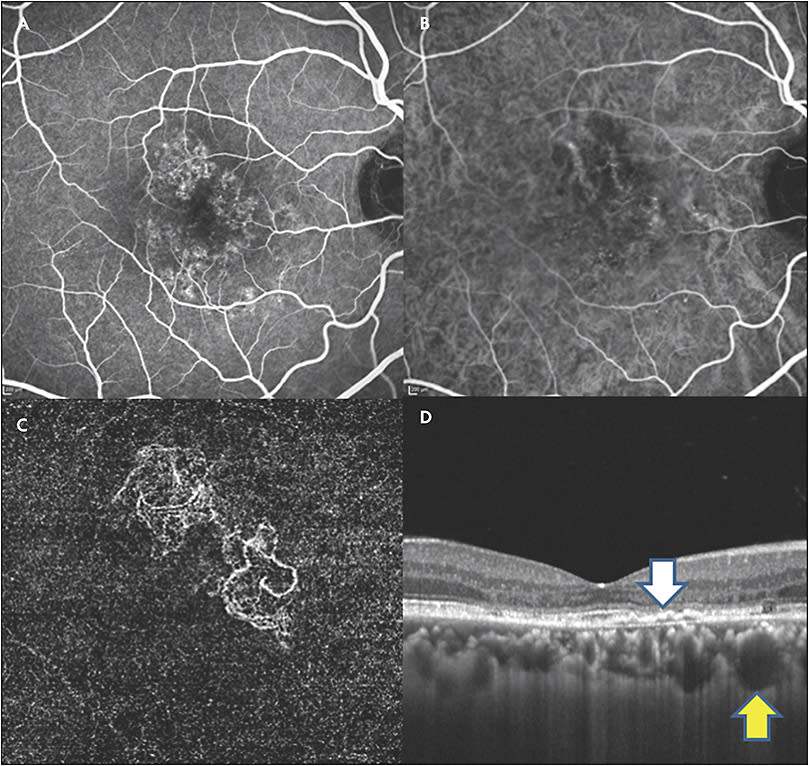

Figure 1 shows diagnostic imaging of a 47-year-old male patient referred for the diagnosis of chronic CSR. Given the thick choroid, young age, and evidence of exudation, he was treated with half-fluence photodynamic therapy (PDT) without resolution. Intravenous fluorescein angiography was characteristic of diffuse, nonspecific leakage, and ICG did not show signs of hyperpermeability. Optical coherence tomography angiography was instrumental in appreciating that choroidal neovascularization was present and that anti-VEGF therapy would be required.